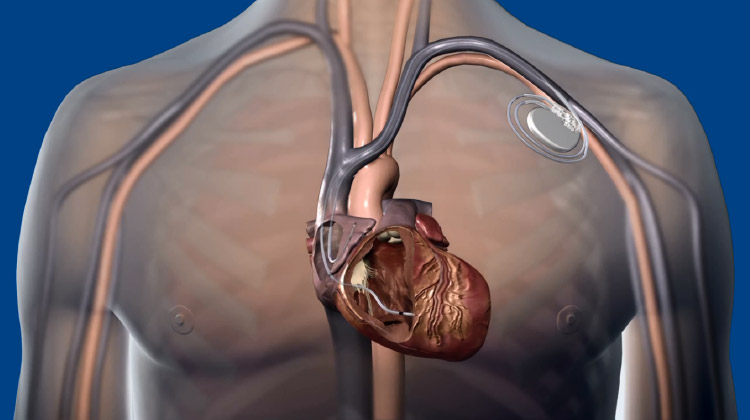

心臓の動きが遅くなる徐脈性不整脈(洞機能不全症候群、房室ブロックなど)には、ペースメーカ植込み術を行います。従来は、心室の先端(右心室心尖部)に電極を置く方法が主流でしたが、この方法では心臓の動きが不自然になり、心不全や心房細動のリスクが高まることがわかっています。

そこで近年注目されているのが、刺激伝導系ペーシング(His束ペーシングや左脚ペーシング)と呼ばれる新しい方法です。これらは、心臓本来の電気伝導経路を利用してより自然に心臓を動かすことができる治療法です。

ペースメーカ埋込み術

Medtronic画像提供